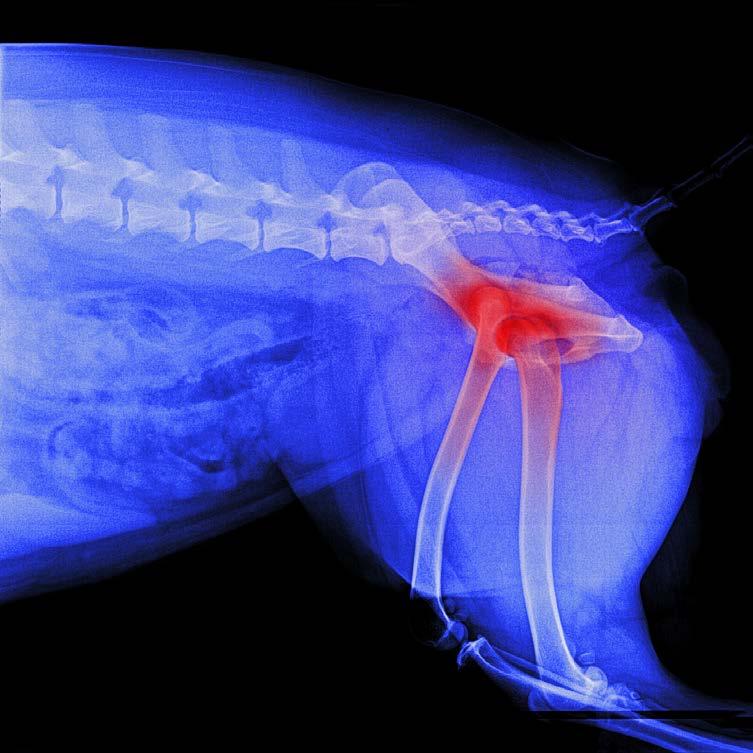

Osteoarthritis (OA) is one of the most common chronic conditions in dogs, and one of the most misunderstood. Many owners attribute stiffness, slowing down or irritability to ‘just getting old,’ when in reality these are signs of pain. Until recently, canine OA treatment options focused mainly on nonsteroidal anti-inflammatory drugs (NSAIDs), joint supplements, weight management and physiotherapy.

But the release of Librella®️ (bedinvetmab) has introduced an entirely new class of pain relief: one that is long-acting, targeted, and specifically designed for chronic arthritis in dogs. If your dog has OA or is showing early signs, this medication may be part of the future of comfort-focused care.

Your vet may recommend it if your dog:

• Shows stiffness after resting

• Becomes reluctant to jump into the car or onto furniture

• Slows down on walks

• Has difficulty standing up

• Becomes grumpy when touched

• Shows lameness that comes and goes

Earlier intervention leads to better outcomes, and many vets are now using Librella®️ as part of multimodal pain management, even in early OA.

7. DECLINING MOBILITY, OR SUDDEN SLOWING DOWN

A dog who struggles to rise, hesitates on stairs, stops jumping onto furniture, or tires on walks is not just ‘getting old.’

Possible causes:

• Arthritis

• Muscle loss

• Spinal pain

• Neurological conditions

What to do: Early pain management is crucial. Joint supplements, anti-inflammatory medication, physiotherapy, and strengthening exercises can dramatically improve quality of life.